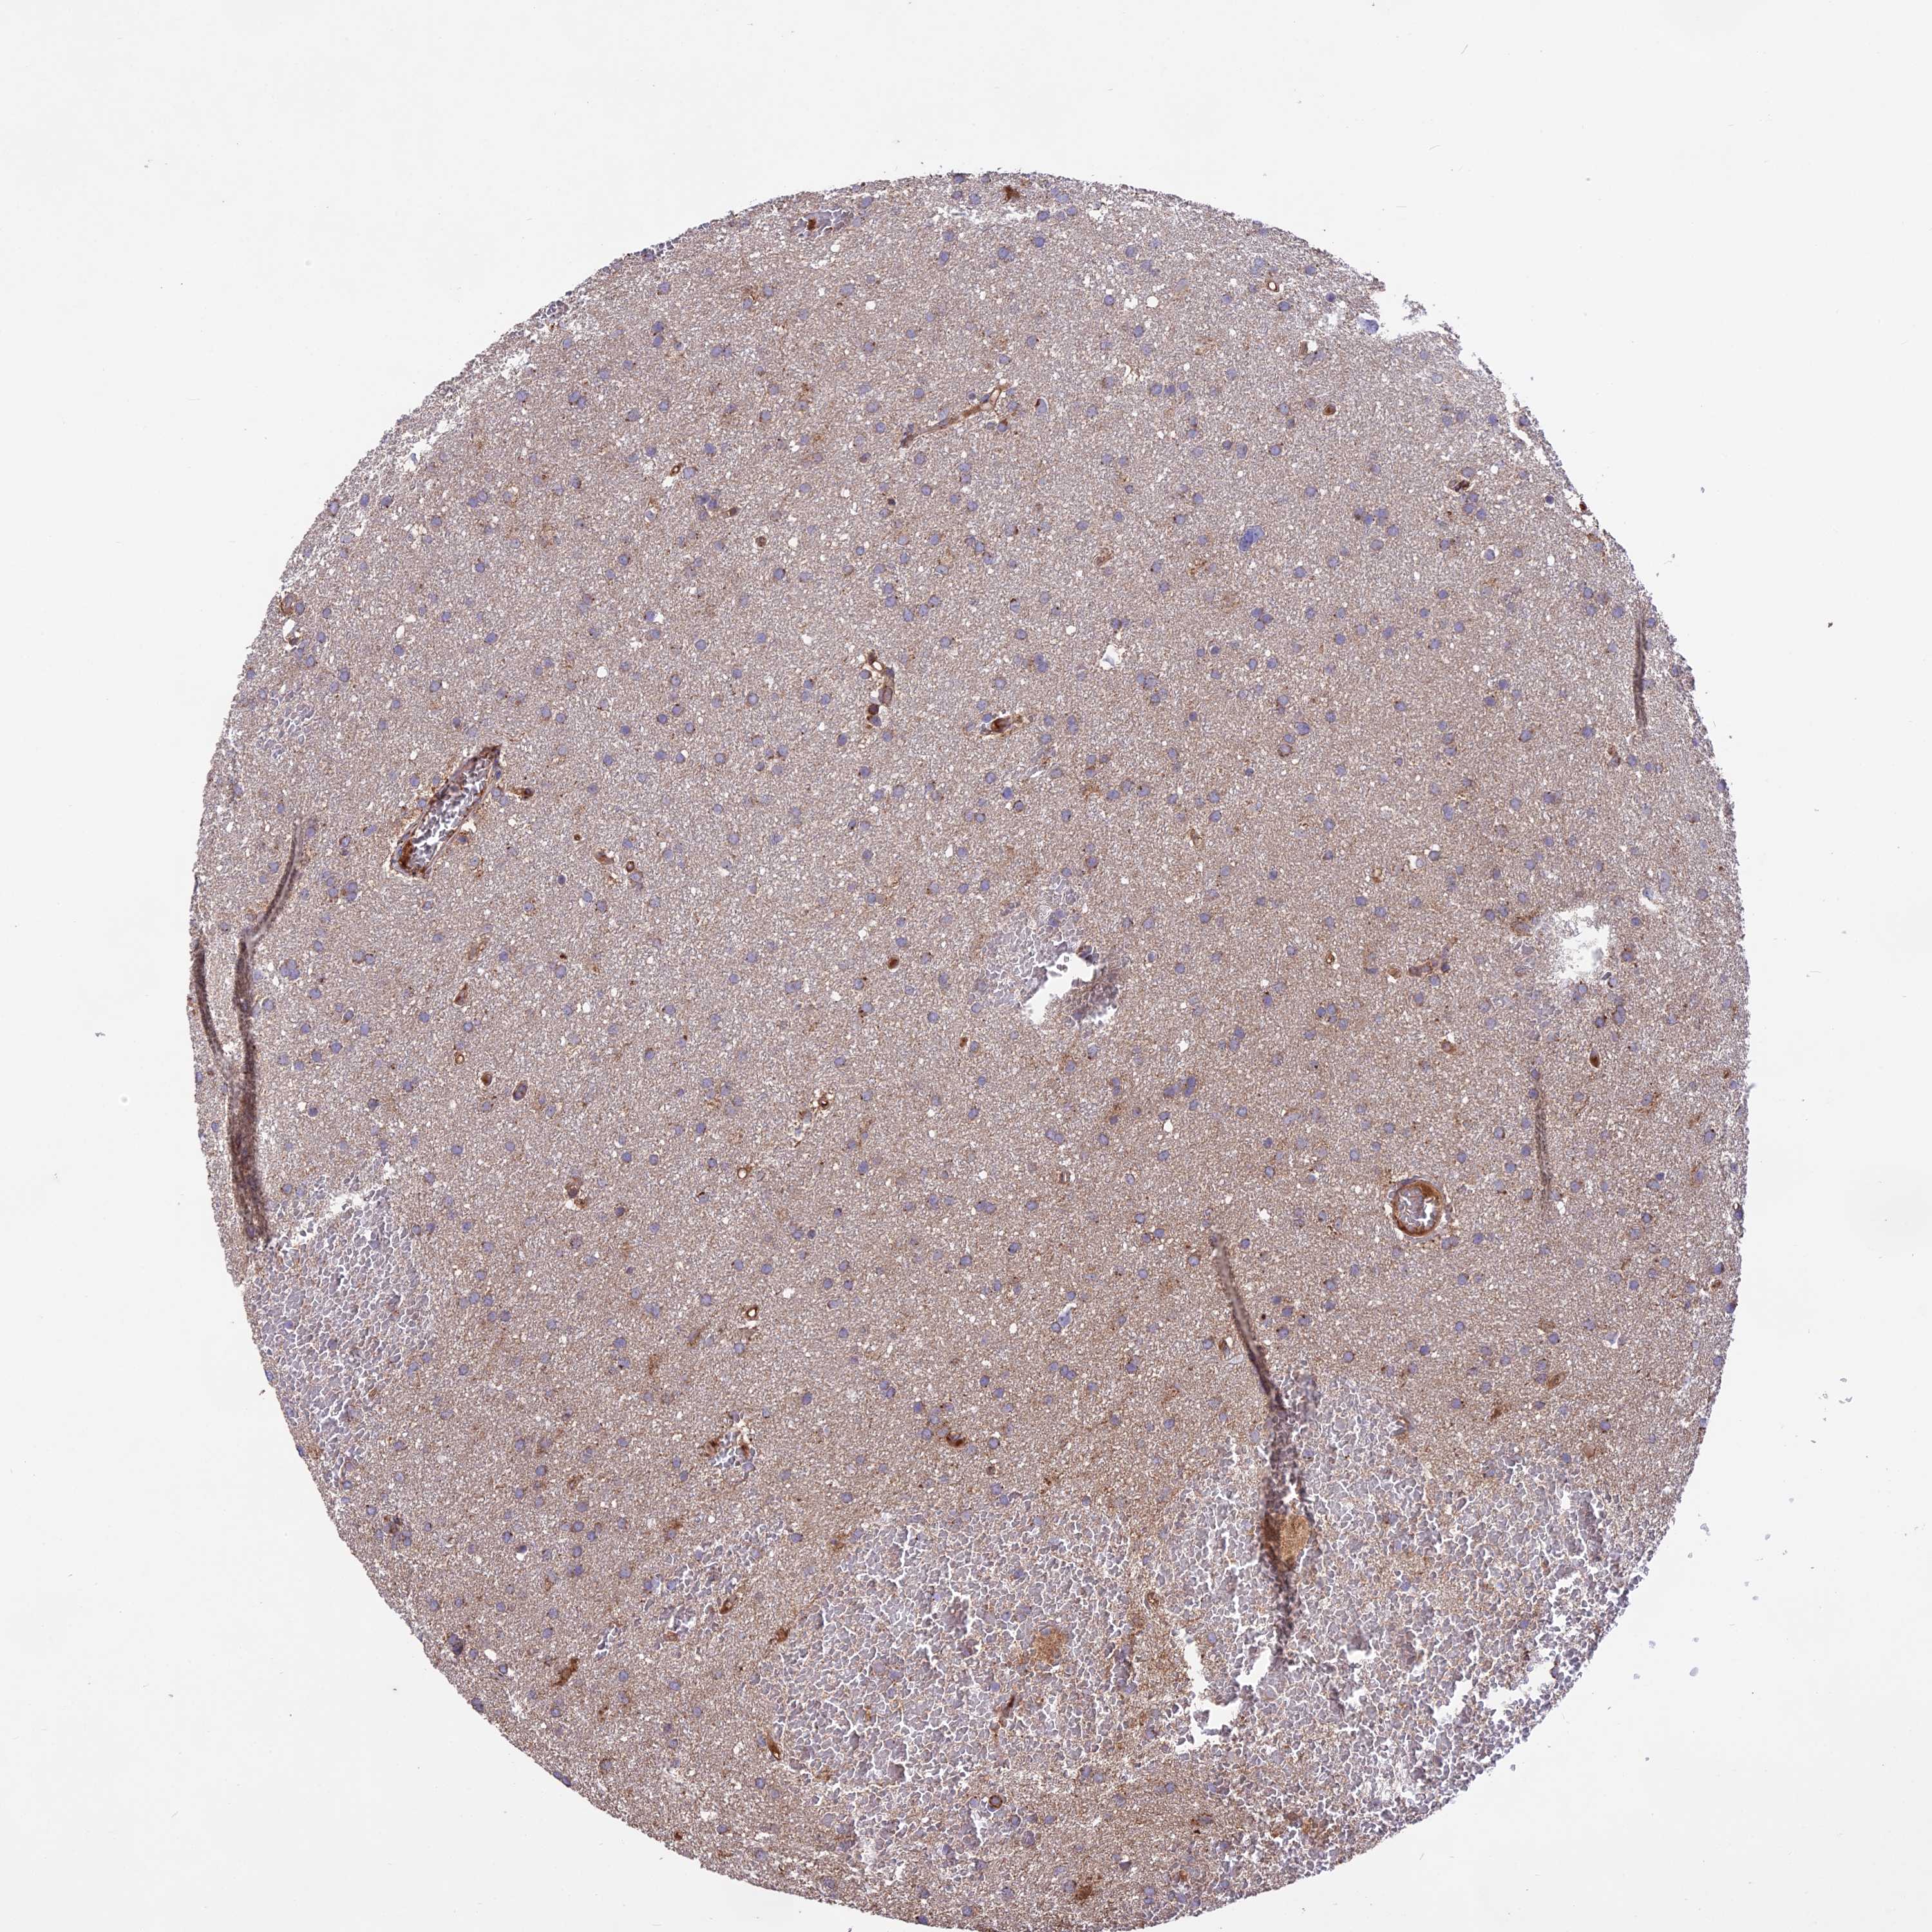

GLIOMA - Protein expressioni

A mouse-over function shows sample information and annotation data. Click on an image to view it in a full screen mode. Samples can be filtered based on level of antibody staining by selecting one or several of the following categories: high, medium, low and not detected. The assay and annotation is described here.

Note that samples used for immunohistochemistry by the Human Protein Atlas do not correspond to samples in the TCGA dataset.

Antibody stainingi

Antibody staining in the annotated cell types in the current human tissue is reported as not detected, low, medium, or high, based on conventional immunohistochemistry profiling in selected tissues. This score is based on the combination of the staining intensity and fraction of stained cells.

Each image is clickable and will lead to virtual microscopy that enables deeper exploration of all samples and also displays staining intensity scores, fraction scores and subcellular localization as well as patient and tissue information for each sample.

Antibody HPA041252

Antibody HPA041466

Glioma, malignant, High grade

Glioma, malignant, Low grade